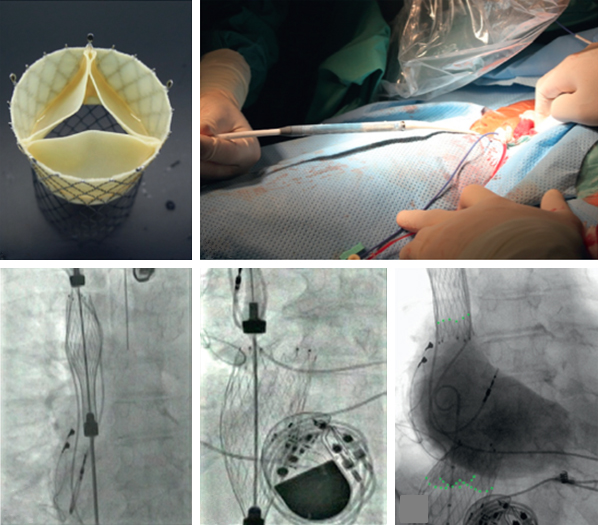

그림 5. MitraClip® system